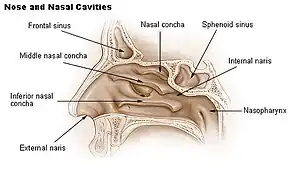

In humans, the conchae divide the nasal airway into four groove-like air passages, and are responsible for forcing inhaled air to flow in a steady, regular pattern around the largest possible surface area of nasal mucosa. As a ciliated mucous membrane with shallow blood supply, the nasal mucosa cleans and warms the inhaled air in preparation for the lungs.

Conchae are composed of pseudostratified columnar, ciliated respiratory epithelium with a thick, vascular, and erectile glandular tissue layer.[4] The conchae are located laterally in the nasal cavities, curling medially and downward into the nasal airway. Each pair is composed of one concha in either side of the nasal cavity, divided by the septum.[4]

The superior conchae are smaller structures, connected to the middle conchae by nerve-endings, and serve to protect the olfactory bulb. The superior conchae attach to the ethmoid bone. The openings to the posterior ethmoidal sinuses exist under the superior meatus.[3] The sphenoid sinus ostium exists medial to the superior turbinate.[5]

The middle conchae are smaller but have the most complex anatomy of the nasal turbinates. They originate from the lateral edge of the cribriform plate of the ethmoid bone. They insert anteriorly into the frontal process of the maxilla and posteriorly into the perpendicular plate of the palatine bone.[6] There are three mutually perpendicular segments of the middle turbinate: from proximal to distal, there is the horizontal segment (axial plane), the basal lamella (coronal plane), and the vertical segment (sagittal plane). They project downwards over the openings of the maxillary and anterior and middle ethmoid sinuses, and act as buffers to protect the sinuses from coming in direct contact with pressurized nasal airflow. Most inhaled airflow travels between the inferior concha and the middle meatus.[3] In humans, they are usually as long as the little finger.

The inferior conchae are the largest turbinates, can be as long as the index finger in humans, and are responsible for the majority of airflow direction, humidification, heating, and filtering of air inhaled through the nose.[3]